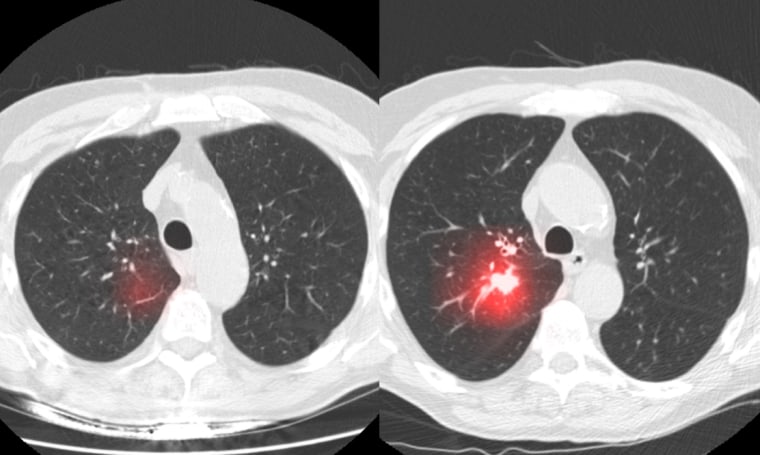

Artificial Intelligence (AI) is transforming the way infectious diseases are detected, diagnosed, and monitored across the healthcare ecosystem. From chest X-rays identifying pneumonia to CT scans assessing tuberculosis severity and AI-driven analytics supporting outbreak response, advanced imaging solutions are becoming indispensable. The AI Powered Infectious Diseases Imaging Market has emerged as a high-growth segment within the broader AI in medical imaging landscape, fueled by rising global infection rates, increasing diagnostic demand, and the need for faster clinical decision-making.

The COVID-19 pandemic acted as a catalyst, accelerating the adoption of AI-enabled radiology tools capable of detecting lung abnormalities within seconds. Today, hospitals, diagnostic centers, and public health agencies are investing heavily in intelligent imaging systems that reduce diagnostic errors, optimize workflow efficiency, and improve patient outcomes. With continuous innovation in deep learning, computer vision, and cloud-based platforms, this market is poised for sustained expansion over the coming decade.

These innovations highlight how AI systems assist radiologists in detecting lung infections, prioritizing urgent cases, and enhancing workflow efficiency.